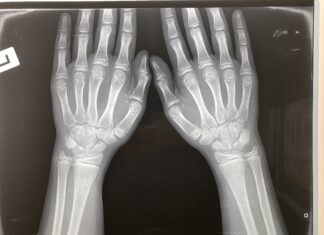

Χ-ΦΥΛΟΣΥΝΔΕΤΗ ΥΠΟΦΩΣΦΟΡΑΙΜΙΚΗ ΡΑΧΙΤΙΔΑ/ΟΣΤΕΟΜΑΛΑΚΥΝΣΗ

Είναι μια σπάνια, γενετική, χρόνια και εξελισσόμενη σκελετική διαταραχή, η οποία χαρακτηρίζεται από αυξημένη αποβολή φωσφορικών από τους νεφρούς, υποφωσφοραιμία, ραχίτιδα και/ή οστεομαλάκυνση και μειωμένη ανάπτυξη.